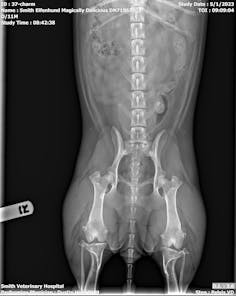

Digital Radiology

We have in-house digital x-ray capabilities which allows our doctors to view the results within seconds. Digital radiographs can be enhanced to provide a better image compared to traditional x-ray films. The images can then be sent to specialists as needed.